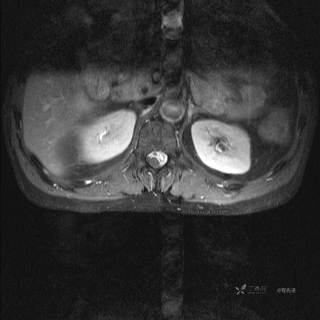

MR

T2

T2压脂

T1

T1增强

T1增强冠状位

T1增强横断位